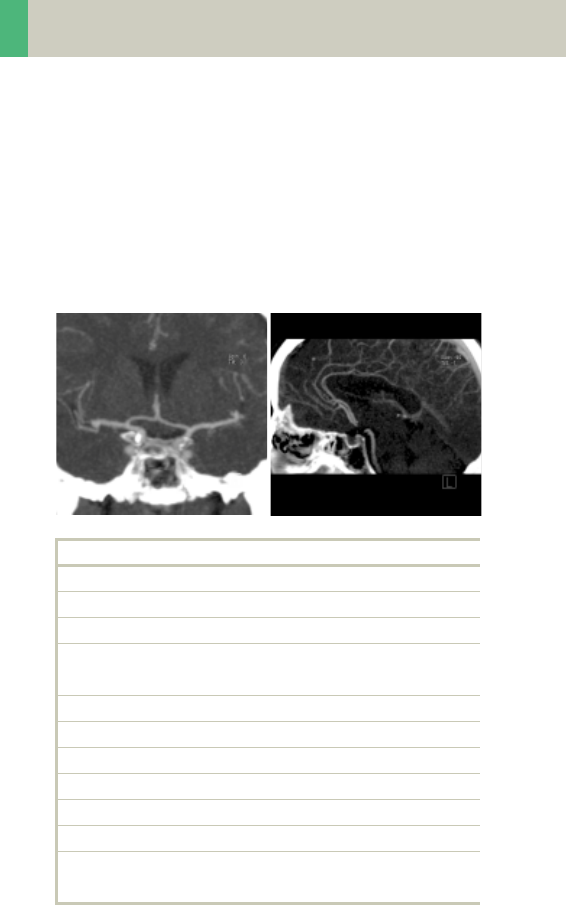

HeadAngio/HeadAngio08s

Indications:

Spiral mode for cerebral CT Angios, e.g., cerebral vas-

cular abnormalities, tumors and follow-up studies etc.

A range of 6 cm will be covered in 32/26 sec.

HeadAngio 2

nd

reconstruction

kV 130

Effective mAs 50

Rotation time 0.8/1.0 sec

Slice

collimation

1.0 mm

Slice width 3.0 mm 1.25 mm

Feed/Rotation 2.0 mm

Pitch Factor 1.0

Increment 3.0 mm 0.8 mm

Kernel H31s H31s

CTDIVol 11.39 mGy

Effective dose Male: 0.26 mSv

Female: 0.30 mSv